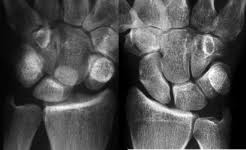

Bei einem Außenbandriss im oberen Sprunggelenk dauert es - abhängig von der Schwere der Bandverletzungen - zwischen vier und zwölf Wochen bis die Stabilität des Gelenks wieder vollständig hergestellt ist Formen von Bänderrissen. Hier genügt es meist das Handgelenk über vier bis sechs Wochen ruhigzustellen damit das Band ausheilen kann. Wie lange dauert der Heilungsprozess.

Ein gerissenes SL-Band bedeutet für das Handgelenk einen empfindlichen Stabilitätsverlust. Wie lange die Heilung eines Bänderrisses dauert hängt von der Nachbehandlung Schonung und Wundheilung ab. Wie lange ein Bänderriss am Handgelenk bis zur vollständigen Ausheilung braucht richtet sich insbesondere nach dem Schweregrad der Verletzung.